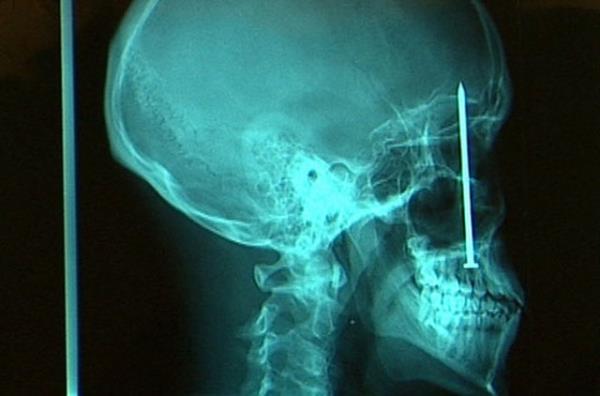

27. Ağzına çivi saplanan hastanın ameliyata alınmadan önce çekilen röntgen filmi...

Ağzına çivi saplanan hastanın ameliyata alınmadan önce çekilen röntgen filmi...